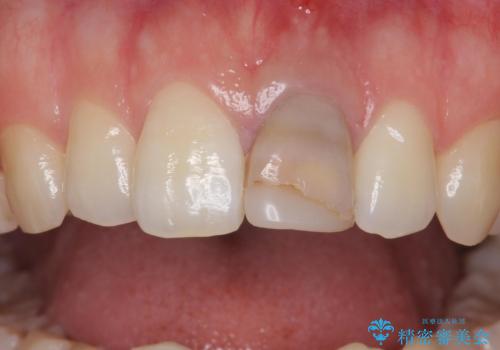

- 前歯の変色を主訴に来院された患者様です。

より審美的な修復を行いたいとのことであったため、ジルコニアクラウンでの修復を行います。

- 左上1 : 仮歯 / 11,000円、ジルコニアクラウン(スペシャル) / 154,000円 合計165,000円(税込)費用は治療当時の料金となります